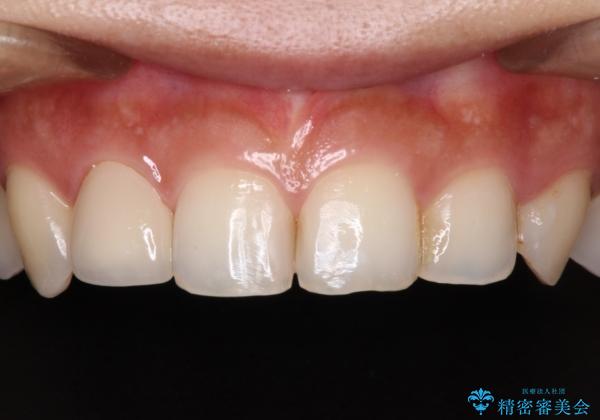

- 冷たいものがしみたり、ものが挟まったり、噛んだときに痛んだりするとのことで来院された患者様です。

銀歯の下のむし歯については、優先度の高い方からセラミッククラウンなどで治療していくこととしました。

治療開始時は右上奥歯と前歯のみが気になっていたのですが、その後下顎左右の奥歯に強い痛みや銀歯の脱離などが頻発し、問題のあるところは全て治療を行うこととしました。